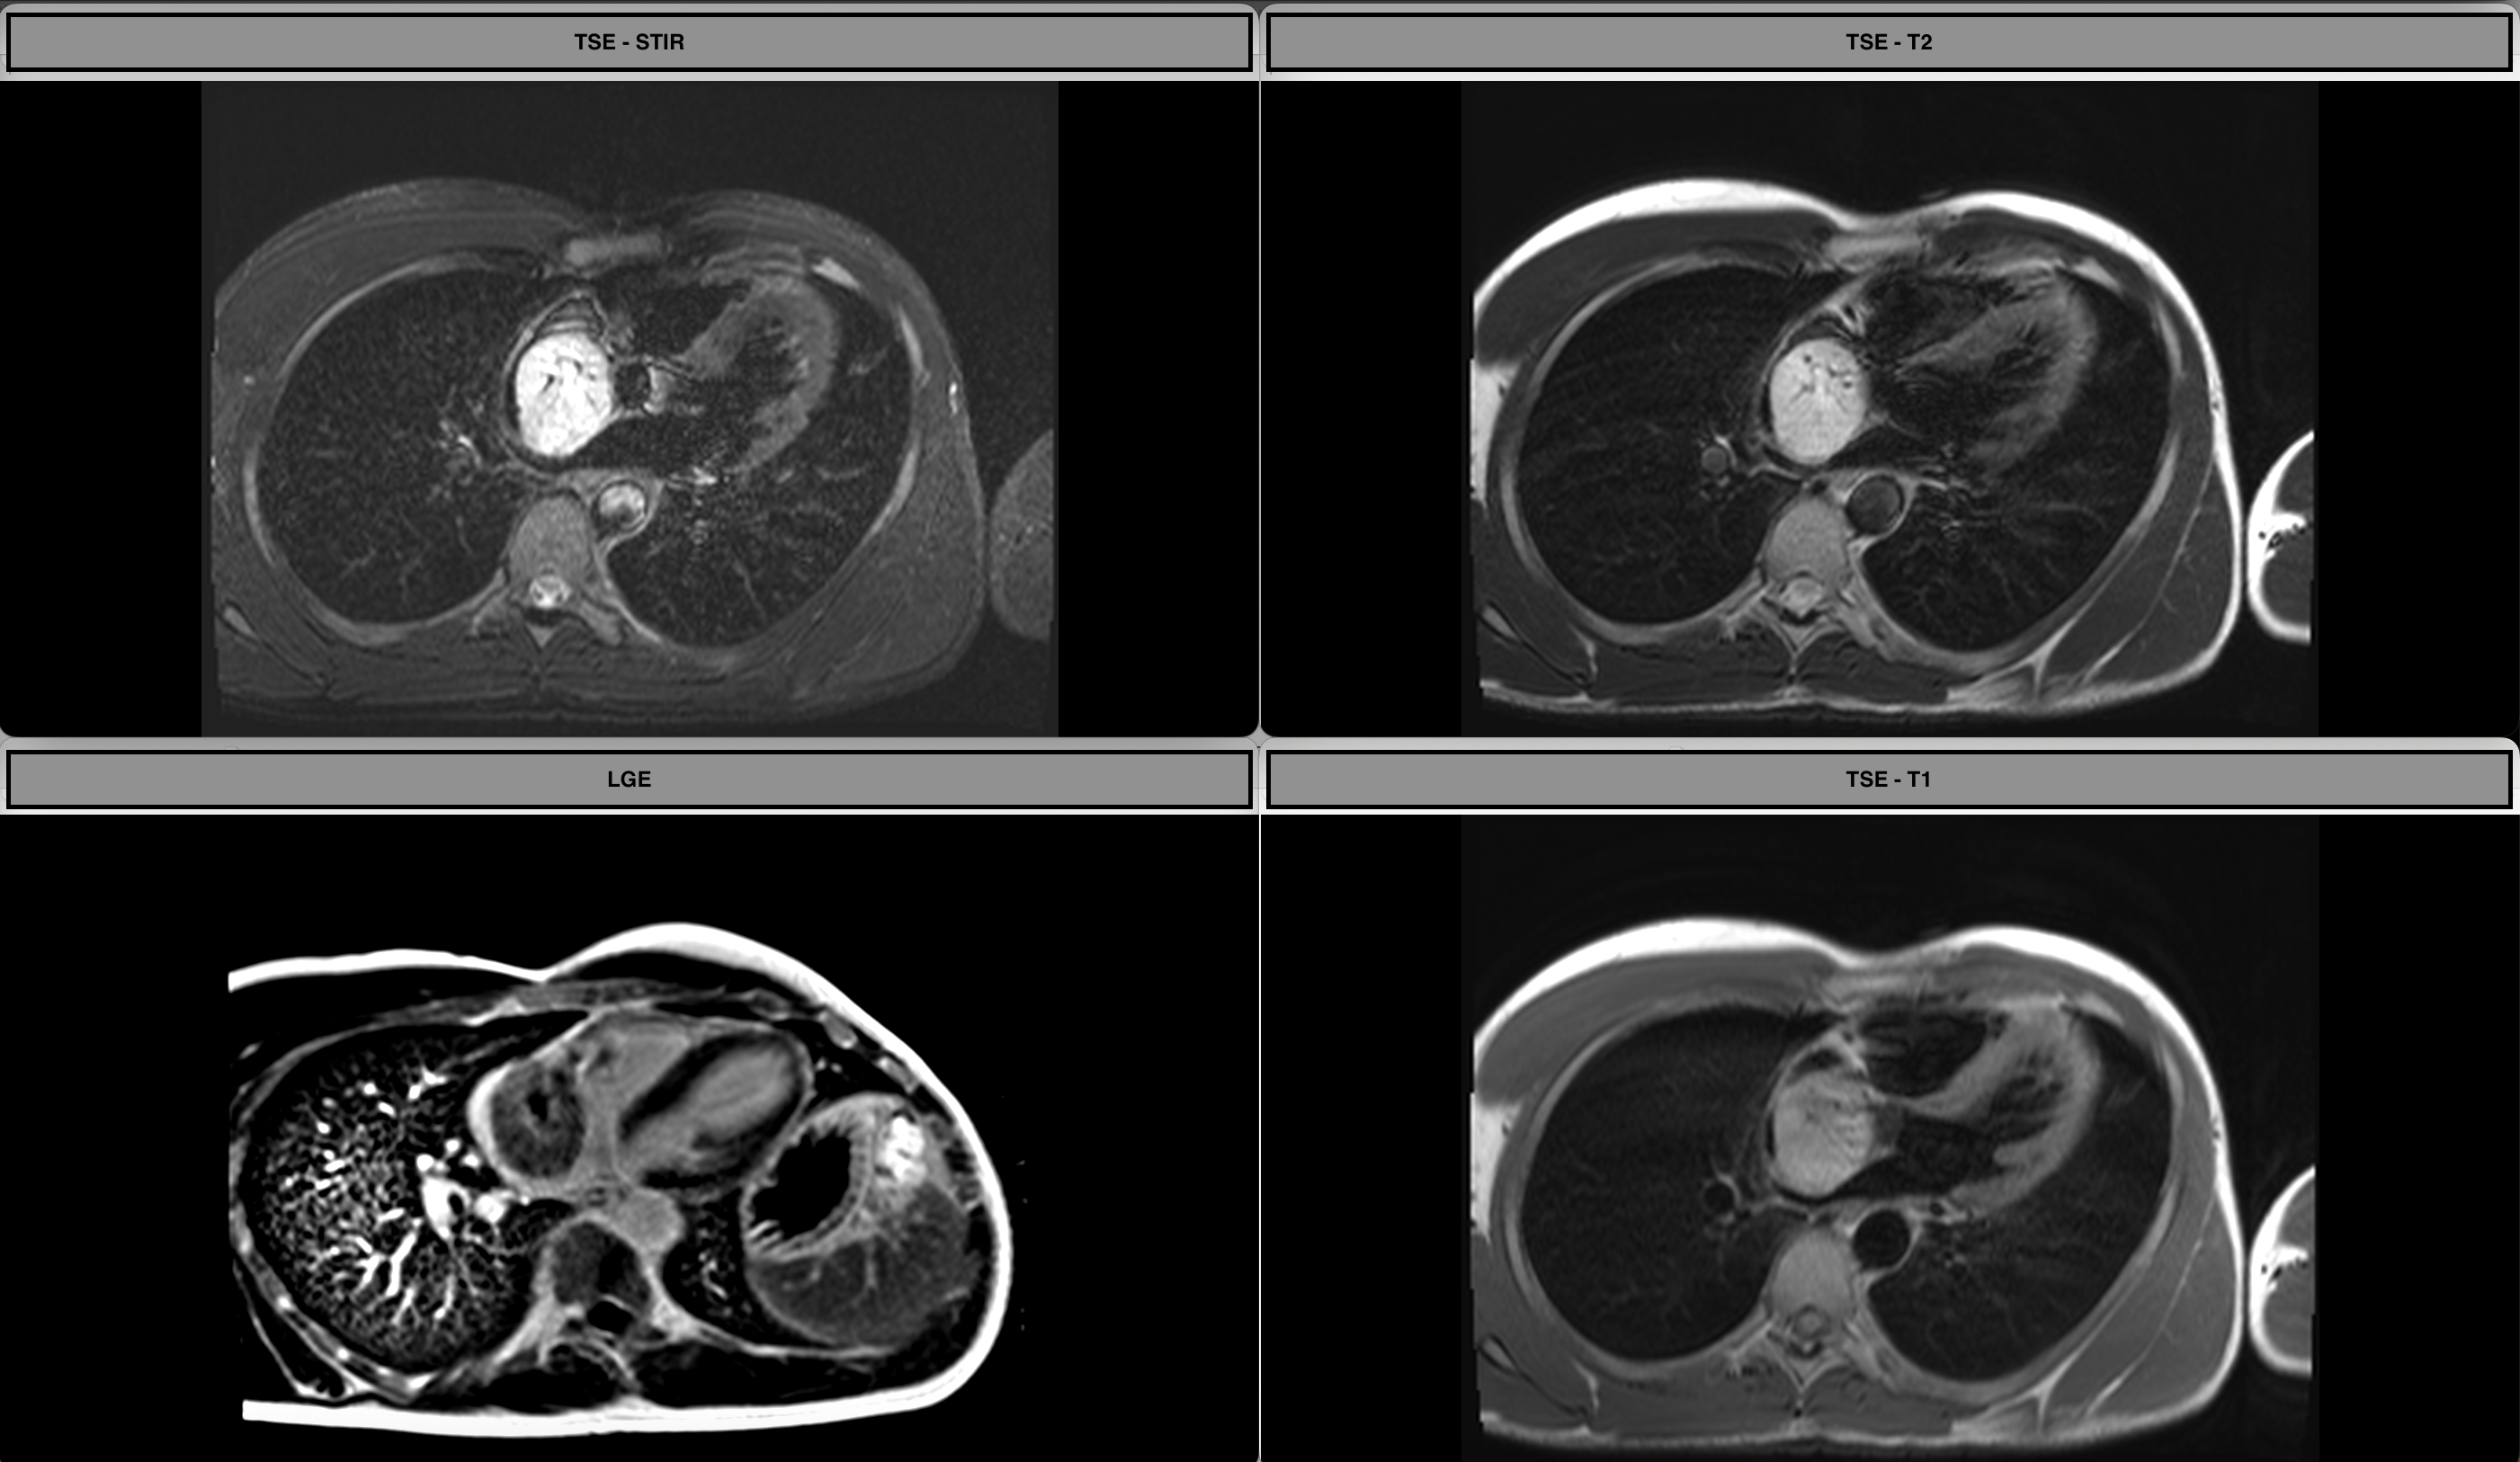

First-pass Perfusion

Cines